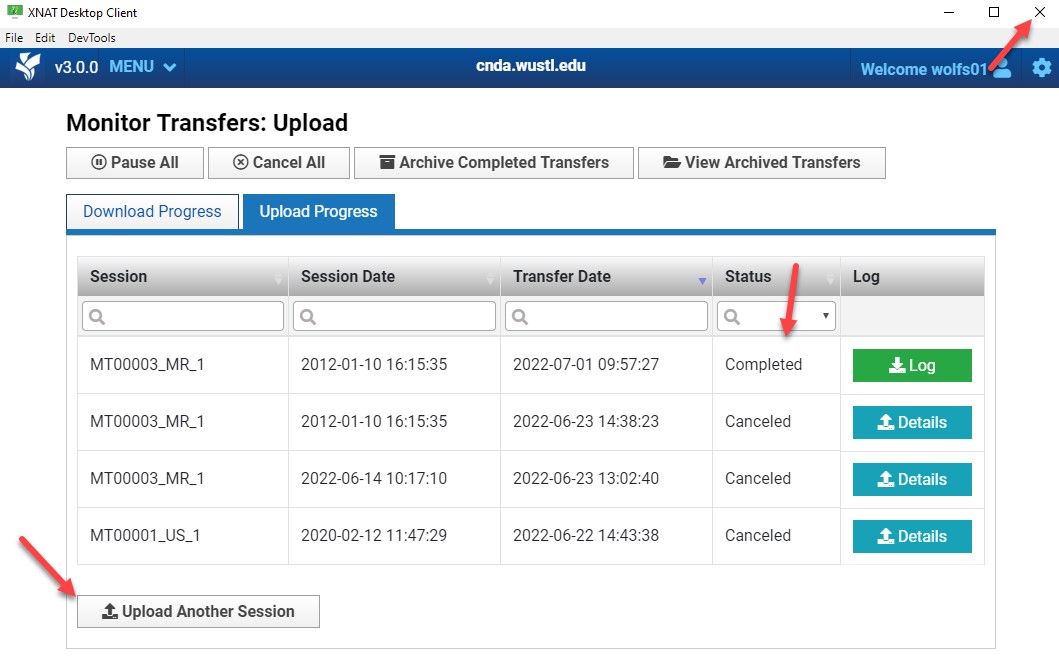

Monitor Upload Progress

The Monitor Transfers page displays upload status.

When the Status column shows Completed, the upload is finished.

Click Upload Another Session to upload another session or close the client.